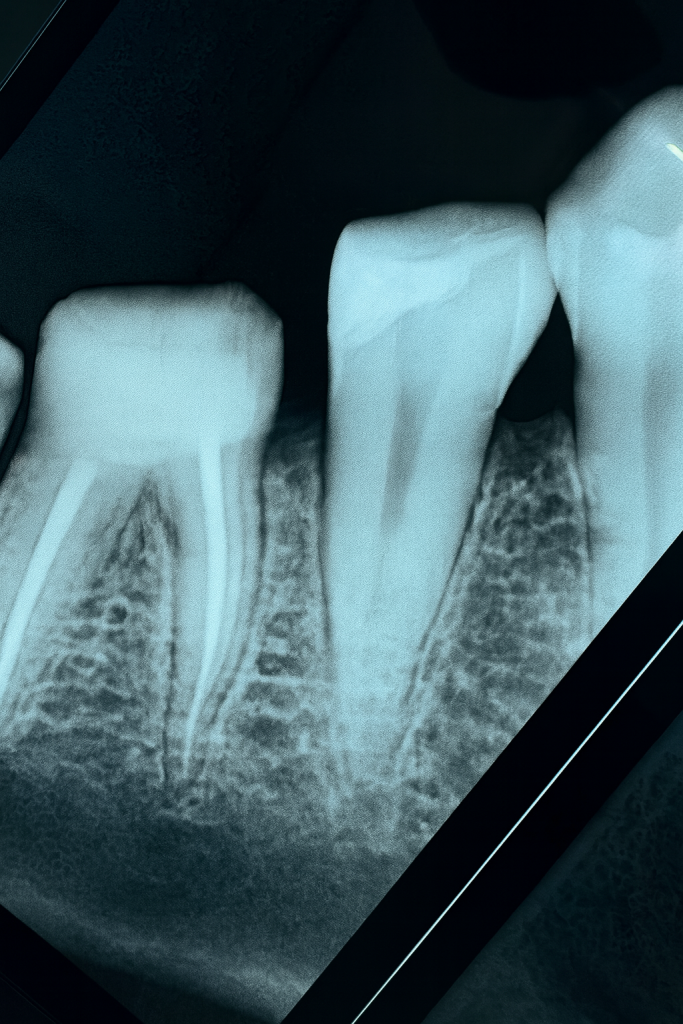

1️⃣ Pre-operative Assessment

Radiographic evaluation revealed deep proximal caries extending sub-gingivally. Tooth was asymptomatic and restorable. (Fig 1)

- Fig 1: Pre-op radiograph showing deep proximal lesion.